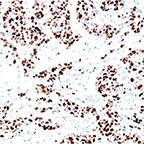

IHC/Antibodies